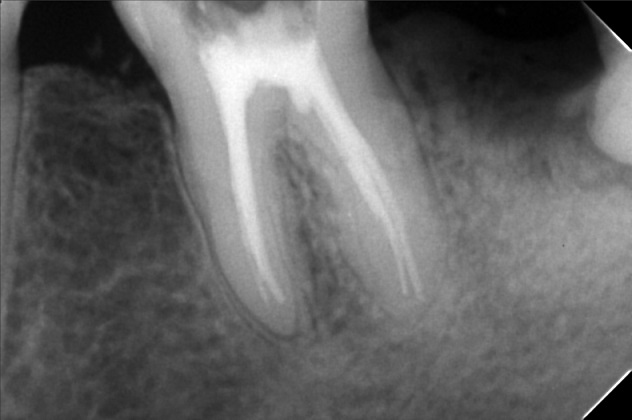

Edit Record Check our patient data records. Add patient information Patient Info Profile picture Last Name First Name Middle Name Birthdate Age Street Barangay City Country Zip Code Contact number Email Procedure 1/14/22- 12,22,36 - Xray LC # 26,27 & OP 1/29/22 - LC #12 - Mesial , lingual, labial LC#11 Surfaces mesial, distal, lingual, labial LC #21 - Mesial 2/19/22- exo 37 *for rct 4 canals 36 2/25/22 DB 21mm DL 22 mm MB 20.5mm ML 20mm formocresol with eugenol 2/05/22- camphenol/ white file *no sensitivity to hot and hold and during auscultation/ TF 2/12/22- no more pain. no more sensitivity/camphenol **next meeting xray. laser/ obturation 3/18/22- laser/ obturation/filling with fiber/ occlusal/ buccal/ lingual/mesial *observe 03/22/22- mbt 0.22/ 14 niti Ul/ class 3/ crowding ceph/ pano/ intraoral/ extra oral photos/ *** to ff up- cast analysis with ortho brush and wax 4/22/22- 14 niti UL RW #31 05/21/22 adj same wire/ req for ceph for exo Pm upper LR 7/2/22- Same wire 14 niti U/L RPI 22 Distal w/ RW Request Tad fot 4th Q 07/28/2022-U 0.016SS; placed ocs bet 11 and 13. L 0.016NITI; changed ligaties only. 08/27/22- SAME WIRE/ rpi 13/22 9/29/22 - RPI #21/#22, U 16ss wire, CHAIN #13-#15, INDIV #12-26; L SAME WIRE INDIV 11/04/22-ADJ/reattached 12/2/22- adj/1 reattached #36 01/13/23-adj 04/17/23- adj 16ss U indi/18 ss L chain 05/13/-23- U - same wire, individual/L - 16 ss, chain/Resto #11D class III 06/16/23- ortho UL same wire, U: individual L: chain RW # 31M 07/15/23- 18 ss U/ Rw 11M/ same wire lower chain lower closing space 08/15/23- closing space/ same wire ***for Lc 14/15/16 09/19/23- same wire/ chain upper/ chain 32-35 chain 11/12/24- ipr 11/21 DISTAL/ CLASS II ELASTIC chipmunk for TADS - 3500 01/27/24- same wire chain upper reattached # 02/28/24 -same wire -reattach #14 03/27/24 16x22 lower chain U RW #42 mesial for removal for the month of june 04/27/24 #14 reattached- no charge same wire chain U/ chain #33-34 05/28/24 16x22 U/L chain 32,34 class II elastic one quadrant II to III chipmunk 06/28/24 removal of brace File 300986490_754411172436439_2707532318128906720_n.jpg File 2 299958020_854700088834251_2016017323265959674_n.jpg File 3 302089664_596777748599375_6189577205987709592_n.jpg File 4 302471710_409703067737285_7864073801397539615_n.jpg File 5 302092198_453164560086776_1373823481126109582_n.jpg File 6 espiritu.jpg File 7 michael_espiritu.jpg File 8 michael_espiritu_1.jpg File 9 File 10 File 11 File 12 File 13 File 14 File 15 File 16 File 17 File 18 File 19 File 20 Retain Record Retain Record Yes No Save Your Changes